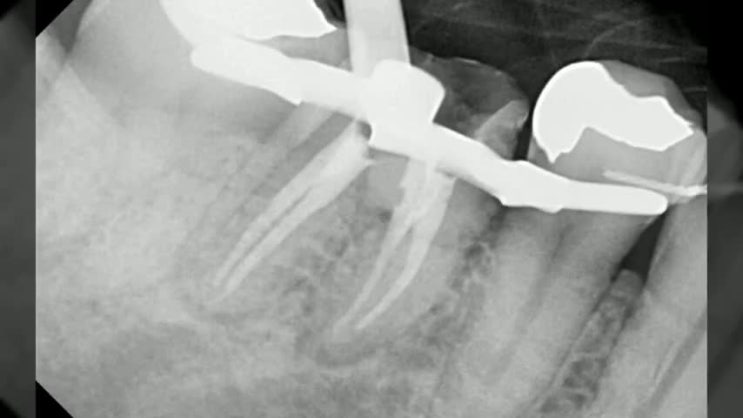

사랑니잇몸염증으로 인한 통증과 부음 ! 사랑니 옆치아 충치로 인해 신경치료까지 진행한 증례

사랑니잇몸염증으로 인한 통증과 부음 ! 사랑니 옆치아 충치로 인해 신경치료까지 진행한 증례 안녕하세요~...